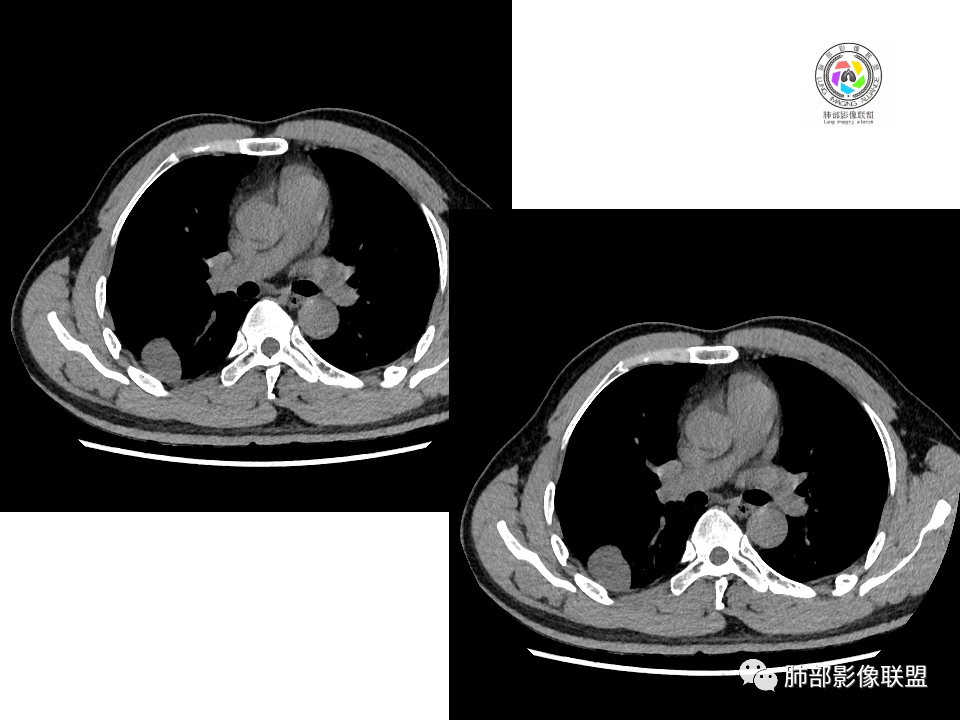

右肺下叶背段胸膜下见团块影,边缘清,其后基底段见一扁平状结节,各见‘’平直及桃尖"征,均轻度强化,右肺上叶背段及中叶外侧段分别少许纤维化灶及部分卫星病灶,一元考虑TB,与隐球菌鉴别!

右肺下叶胸膜下类圆形团块,边缘光滑无毛刺分叶,强化均匀无坏死,另血管旁小结节平直桃尖,上叶小斑片影,考虑结核或者真菌感染。

右肺下叶背段胸膜下见一边缘稍模糊、浅分叶结节灶,密度均匀,似乎轻度均匀强化(具体CT值看不出来),与胸膜锐角相贴,似有平直征和桃尖征。此病灶前内侧还有类似小结节,轻度强化,右肺上叶后段有斑片状稍高密度影:考虑良性病变,炎性结节可能。

晨读,右肺下叶背段胸膜下见肿块影,边缘清晰,未见与气管相连通,右下叶见结节影边缘清晰,两处病变密度均匀,同步不明显强化,中叶外侧段斑点状影,树芽征,考虑1良性病变,结核?隐球菌?2淋巴瘤待除外。

右肺下叶背段胸膜下宽基底团块状占位,浅分叶,边界清晰,胸膜下脂肪间隙清晰,背段支气管管壁似乎增厚,未见明显强化。外侧基底段血管束间结节,边界清晰,亦未见明显强化。中叶外侧段见少许树芽征象。纵隔未见明显肿大淋巴结。我先猜个结核。

男性,49岁,体检发现,右肺下叶背段胸膜下见肿块,边界清楚,边缘光滑,胸膜下脂肪间隙存在,有分叶,无毛刺,均匀强化,内无坏死,右肺下叶血管束间不规则实性结节,边界清楚,无明显强化,中叶少许斑片状高密度影,纵隔未见明显增大淋巴结,考虑良性病变。

2.右肺下叶背段胸膜下块影,边界清楚光整,上下极见磨玻璃晕,未见明显分叶毛刺和棘状突起,未见胸膜凹陷或胸壁侵入。密度均匀,轻度不均匀强化。未见支气管进入。

3.右肺中叶外侧段胸膜下散在小片影,磨玻璃密度为主,边界不清,支气管相关。符合炎性特征!

4.右肺下叶基底段支气管血管束旁小结节影,边界清楚,强化不明显。注意,这结节在“遥远的”基底段。